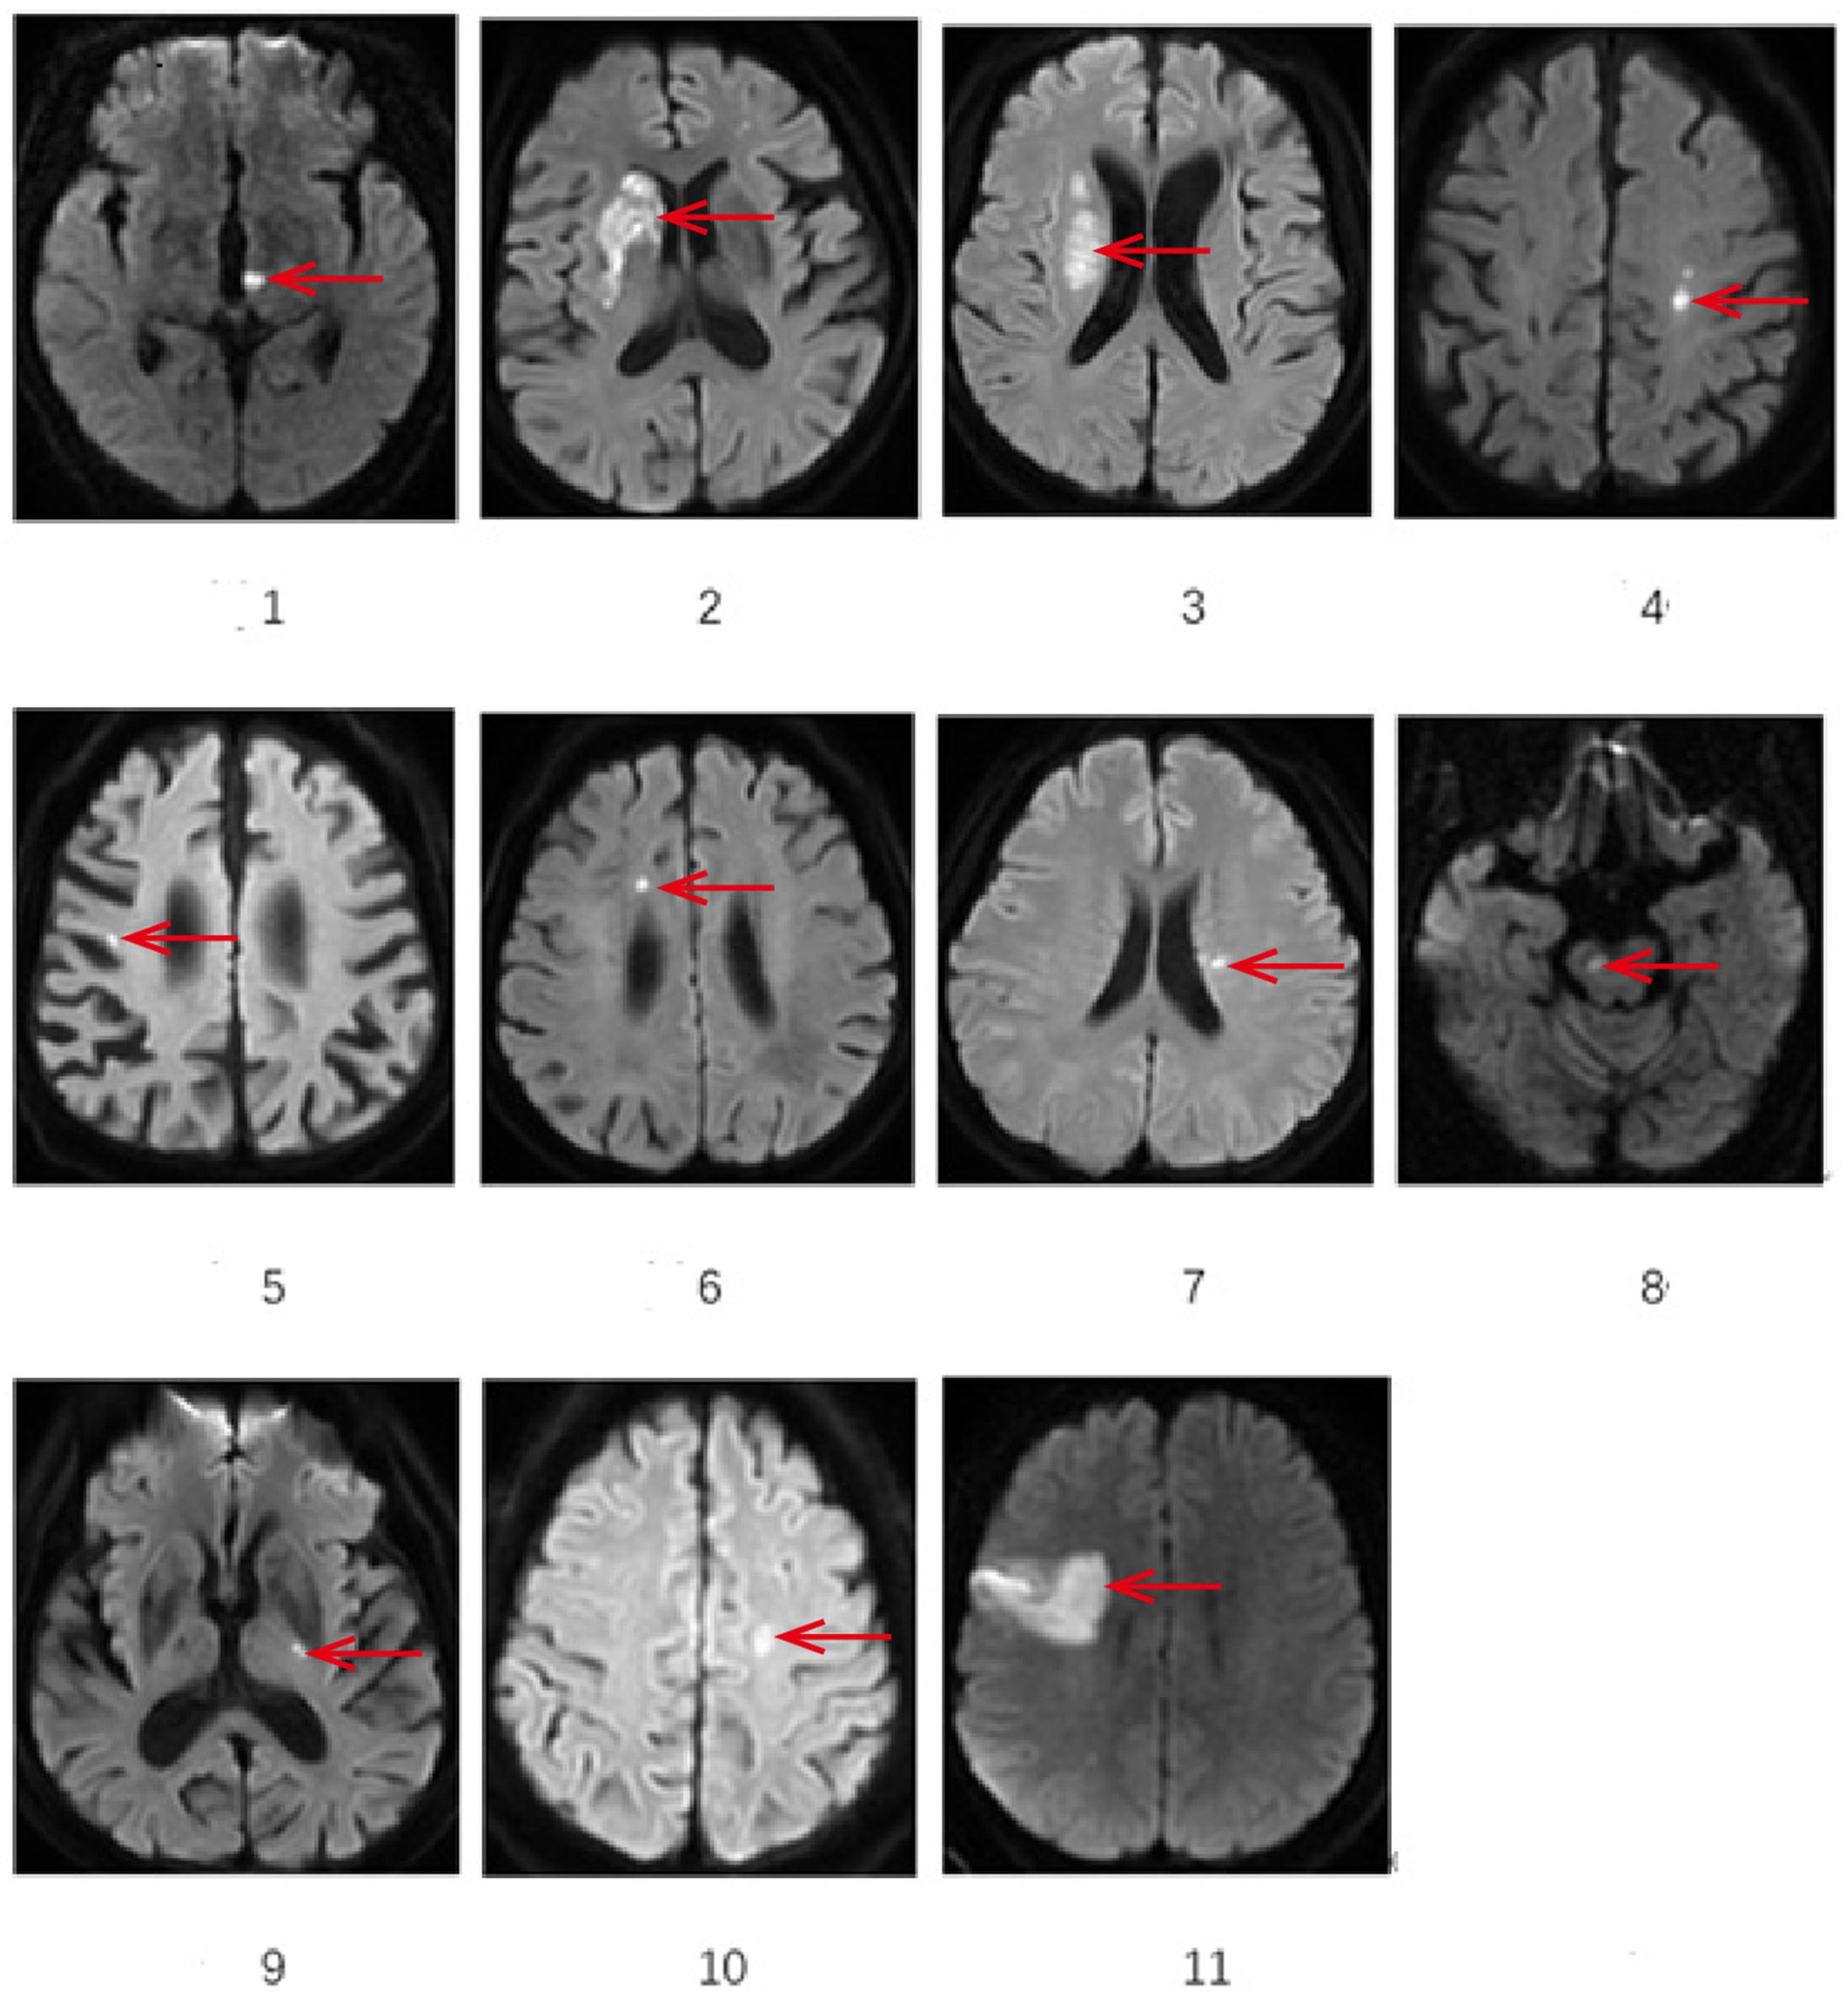

All cases underwent cranial MRI within 1 week of symptom onset. Table 3 systematically presents the triad assessments of neuroimaging characteristics (infarct anatomic location, responsible vascular territory, and etiological classification). Vascular territory analysis revealed: Anterior circulation involvement: 10 cases (90.90%); Posterior circulation involvement: 1 case (9.10%). The location of acute cerebral infarction lesions involves thalamus, basal ganglia, corona radiata (adjacent to or centrum semiovale), frontal lobe, cerebral peduncle of midbrain, and responsible blood vessels involving large artery disease in 7 cases and perforating arteries in 4 cases.Etiological classification CISS: Large artery atherosclerosis (LAA): 6 cases; Penetrating artery disease (PAD): 4 cases; Other determined etiology: 1 case (cerebrovascular malformation confirmed by DSA/MRA). Figure 1 demonstrates the DWI sequence characteristics of infarction lesions on cranial MRI.

Figure 1

Eleven MRI brain scans show different sections with red arrows indicating regions of interest, likely abnormalities or lesions. Each image is labeled sequentially from one to eleven. The arrows point to various brain areas, highlighting distinct patterns or features in each scan.

Figure 1. Demonstrates the representative sections of DWI sequences showing infarction sites on cranial MRI. *The area indicated by the arrow: 1 Left thalamus 2 Right basal ganglia 3 lateral ventricle periphery 4 left centrum semiovale 5 Right frontal lobe 6 Right frontal lobe 7 lateral ventricle periphery 8 Right cerebral peduncle of midbrain 9 Left basal gangli 10 Left centrum semiovale 11 Right frontal lobe.